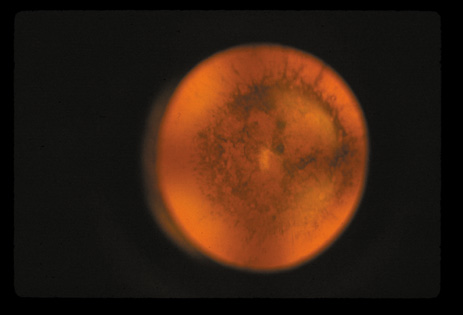

CATARACT ASSOCIATED WITH PRIMARY OCULAR DISEASES

Cataracts can occur secondary to a large number of intraocular diseases. Intraocular inflammation is the most common cause of this type of cataract. These cataracts are typically of the PSC variety. PSCs seen in retinitis pigmentosa (Fig. 31), gyrate atrophy (Fig. 32), and Usher's syndrome (Fig. 33) show finger-like projections. In persistent hyperplastic primary vitreous, the PSC is often associated with abnormal blood vessels from the hyaloid system that arborize from the posterior pole of the lens. Cataracts seen in retinal anoxia and anterior segment necrosis are thought to occur due to interference with the nutrient supplies of the lens. This leads to decreased anabolism, increased catabolism and acidity, and necrosis. The cataracts in these conditions are also of the PSC type. An acute increase in intraocular pressure can cause focal necrosis of the subcapsular epithelium and localized, fleck-like opacities (glaukomflecken). These opacities are initially located immediately under the capsule, but when new fibers are laid down they slowly become buried in the lens. Their presence indicates that the patient has experienced an acute increase in intraocular pressure. The premature occurrence of PSC and possibly nuclear-type cataracts has been noted in eyes with high myopia (Fig. 34).37–41

Fig. 31. PSC in a 25-year-old man with retinitis pigmentosa. (Courtesy of Muriel Kaiser Kupfer, M.D.)